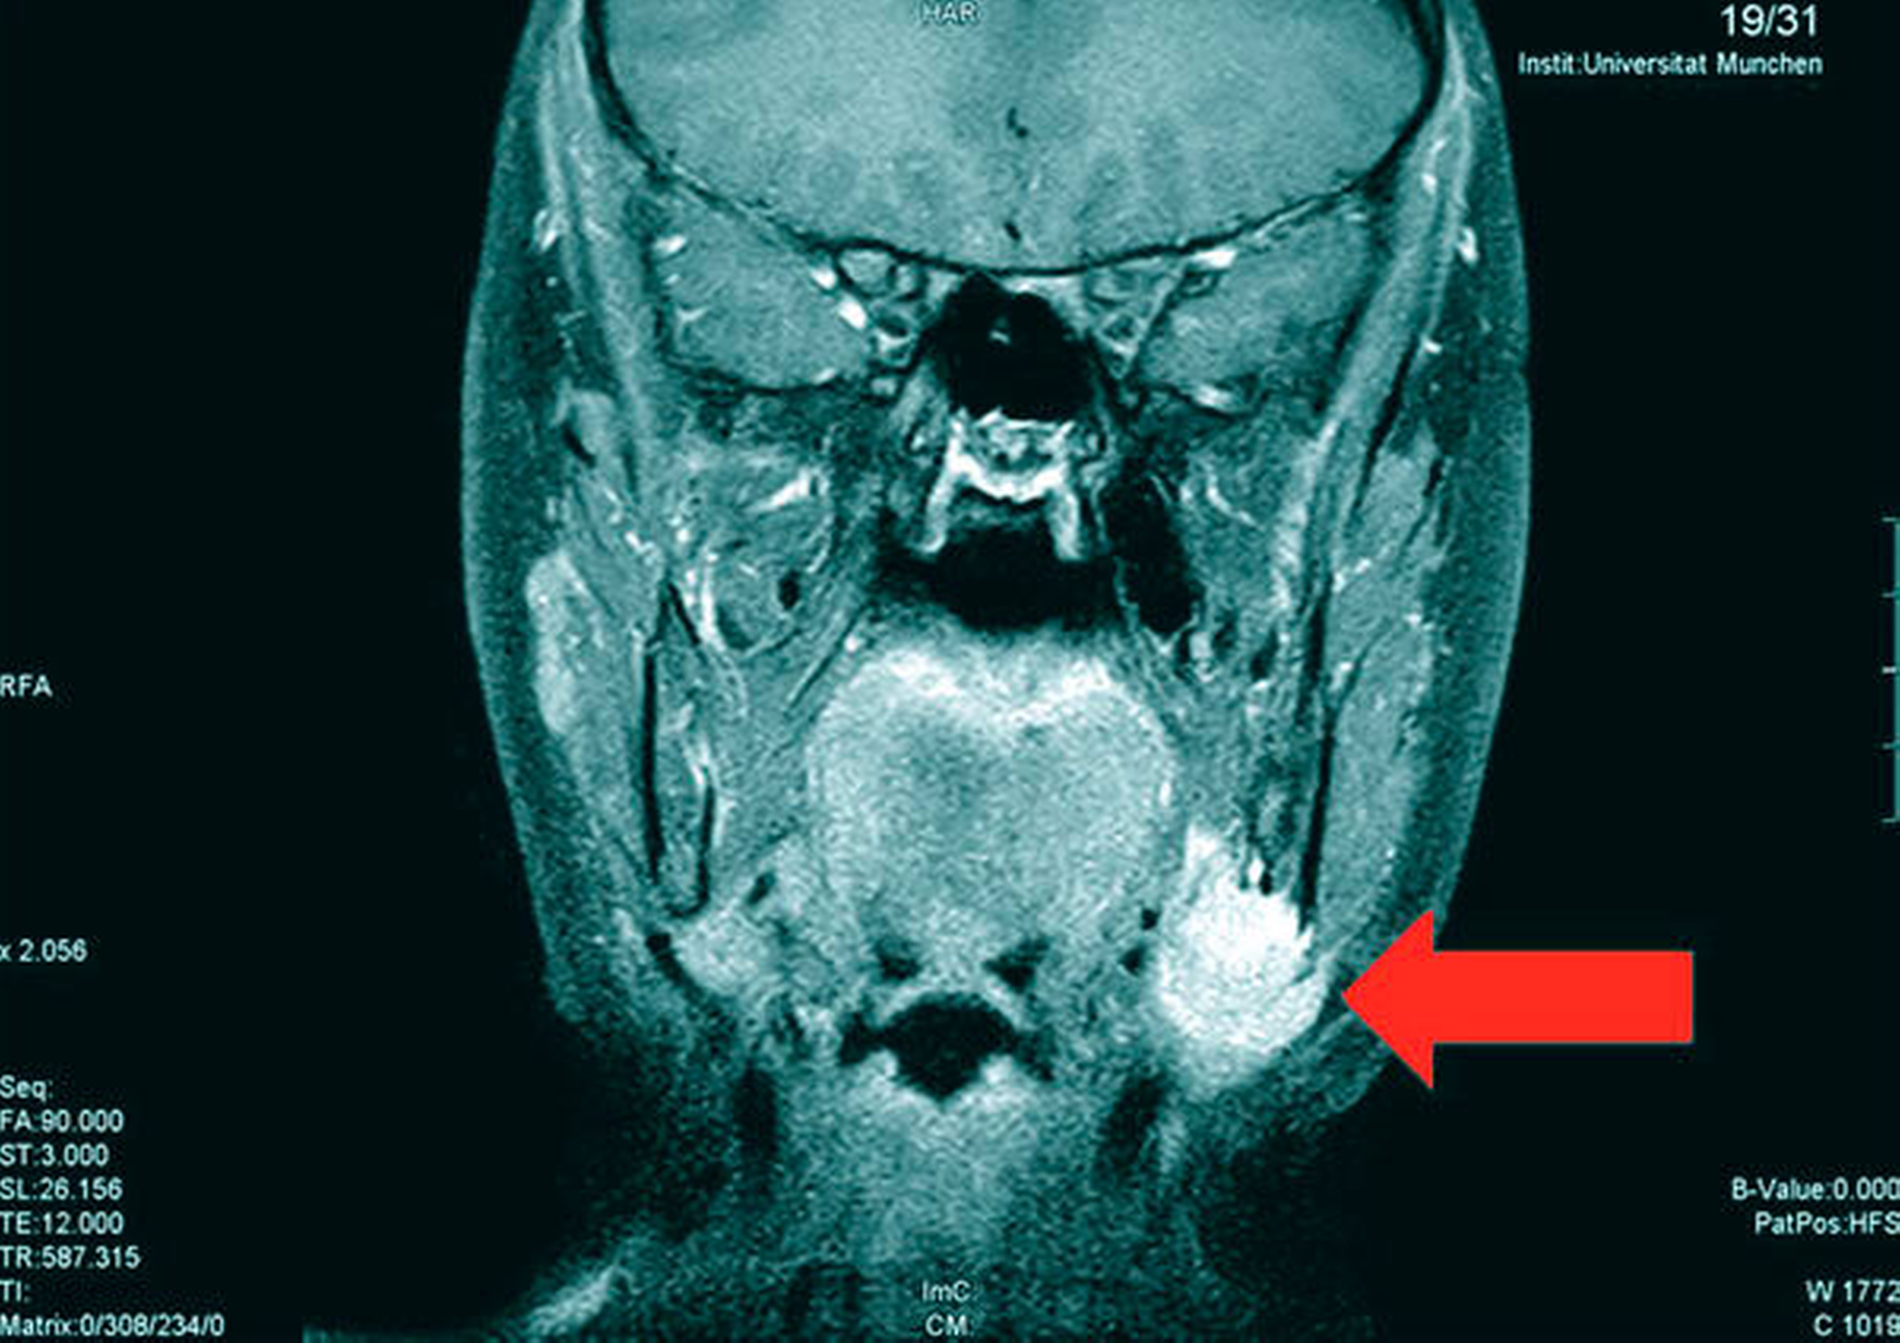

Die Magnetresonanztomografie des Neuro- und des Viszerokraniums erbrachte den Nachweis eines Areals erhöhter Kontrastmittelaufnahme im Bereich des basalen Kieferwinkelrandes links mit einer Ausdehnung von 3,1 cm x 2,3 cm. Im Bereich der behaarten Kopfhaut zeigten sich subkutan T1-hypointense, zum Teil polylobulierte Läsionen mit Verdacht auf epidermale Zysten sowie subgaleale T2-hypointense, flächig kontrastmittelaufnehmende Läsionen mit Verdacht auf Osteome (Abbildungen 3a bis 3d).